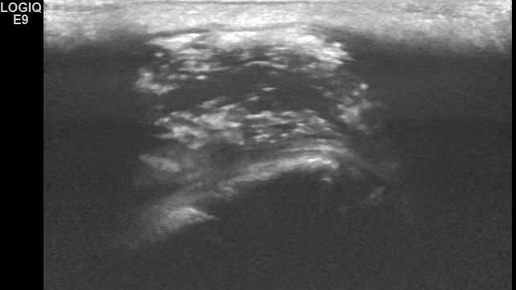

Видео к статье "киста копчикового хода"https://dzen.ru/a/Z_DfZyPUs2uL0hjv

Ультразвуковые находки от врача УЗД Зорина Я.П.